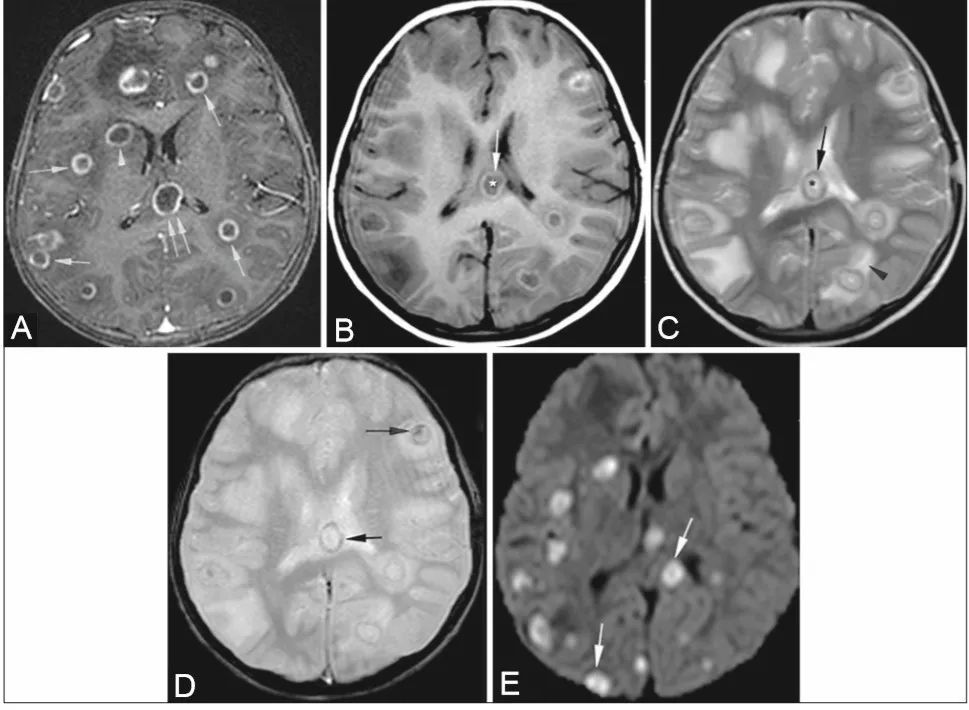

轴向DWI 显示侧脑室室管膜表面弥散受限(A)。相应的T1WI有轻微增强(B)。FLAIR (C)及T1WI 增强扫描(D)显示两侧葡萄膜增厚,右侧视网膜脱离。

成人机会性巨细胞病毒脑室脑炎的影像学表现是非特异性的。巨细胞病毒性视网膜炎和胃肠道受累是巨细胞病毒性感染的常见形式,但在所有巨细胞病毒性感染患者中,神经系统表现仅占不到1%。临床表现为:定向障碍、淡漠、退缩、颅神经病和眼球震颤。脑室脑炎是CMV感染中最常见的中枢神经系统受累形式,其特征是脑室内表面的室管膜炎。CMV引起的视网膜炎发生在大约三分之一没有接受HAART治疗的艾滋病患者中,并占与艾滋病毒感染相关的失明病例的90%以上。主要诊断特征:沿室管膜表面弥散受限伴/不伴造影增强。脉络膜视网膜炎表现为葡萄膜增强、视网膜脱离和视网膜钙化。巨细胞病毒引起的视网膜炎最常见于单眼,并进展到累及对侧眼。要与淋巴瘤和化脓性脑室炎相互鉴别。

增强后T1W像(A):大脑半球多发环形强化病灶(单箭),胼胝体(双箭),右侧基底节(箭头)。T1W图像(B): 核心低信号 (*),高信号环(箭)。T2W图像(C):核心高信号(*),低信号环(箭),周围水肿(箭头)。GRE图像(D):病灶壁和核心出血灶(箭)。DWI (E)显示肉芽肿弥散受限(箭头)。组织病理学:多发性曲霉菌丝和中央坏死。

常见的感染部位包括胼胝体、基底神经节、丘脑和脑干,以及灰白质交界区。常见有以下三种方式:(1)皮质下边界不清的病灶T2呈高信号,T1呈低信号。(2)多发环形脓肿[如本例患者]。(3)靠近主要感染源(如副鼻窦)的硬脑膜异常增强。脓肿在T1W上呈低信号,周围或中央有高信号区,与出血相对应。在T2W上,它们表现为核心高信号,边缘呈低信号。这种低信号环是由真菌凝结形成的,其中含有大量的铁、锰和镁,这些物质存在于真菌菌丝的外围。约25%的病变发生出血,在梯度回波T2W上可以看到晕染区域。